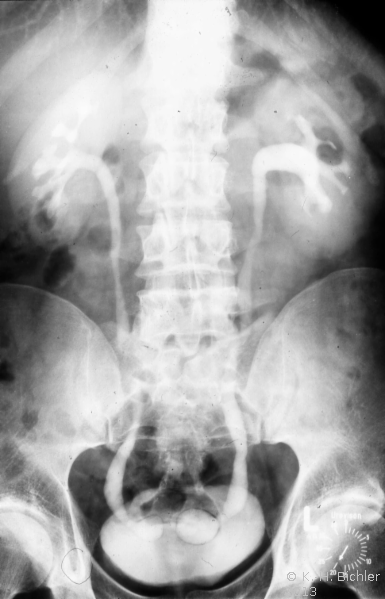

Das Ausscheidungsurogramm tritt bei Kindern und Jugendlichen wegen der relativ hohen Strahlenbelastung als kontrastmittelunterstützte radiologische Untersuchung gegenüber den nichtradiologischen Verfahren in den Hintergrund (eingeschränkte Indikation). Das gilt vor allem für junge Säuglinge, bei denen wegen deren noch schwächeren tubulären Nierenfunktion die Kontrastierung des Urogenitaltraktes nicht ausreicht. Es ist schon gar nicht als Untersuchungsmethode in Standardtechnik zu verantworten. Nach Überprüfung der gesetzlich vorgeschriebenen rechtfertigenden Indikation muss der Untersuchungsablauf fachkundig unter ärztlicher Aufsicht und an die Fragestellung angepasst nach Auswertung der jeweiligen vorausgegangenen Aufnahmen durchgeführt werden.

Literatur:http://www.bundesaerztekammer.de/page.asp?his=1.120.121.1042.5974; Leitlinie zur Qualitätssicherung in der Röntgendiagnostik: Qualitätskriterien röntgendiagnostischer Untersuchungen; Bundesärztekammer Stand: 23.11.2007. Sie schreibt das Verwenden von umschließenden Hodenkapseln, Ovarienabdeckungen und Bleigummiabdeckungen für den an das Nutzstrahlenfeld angrenzenden Körperbereich vor (

10 Abbildungen).